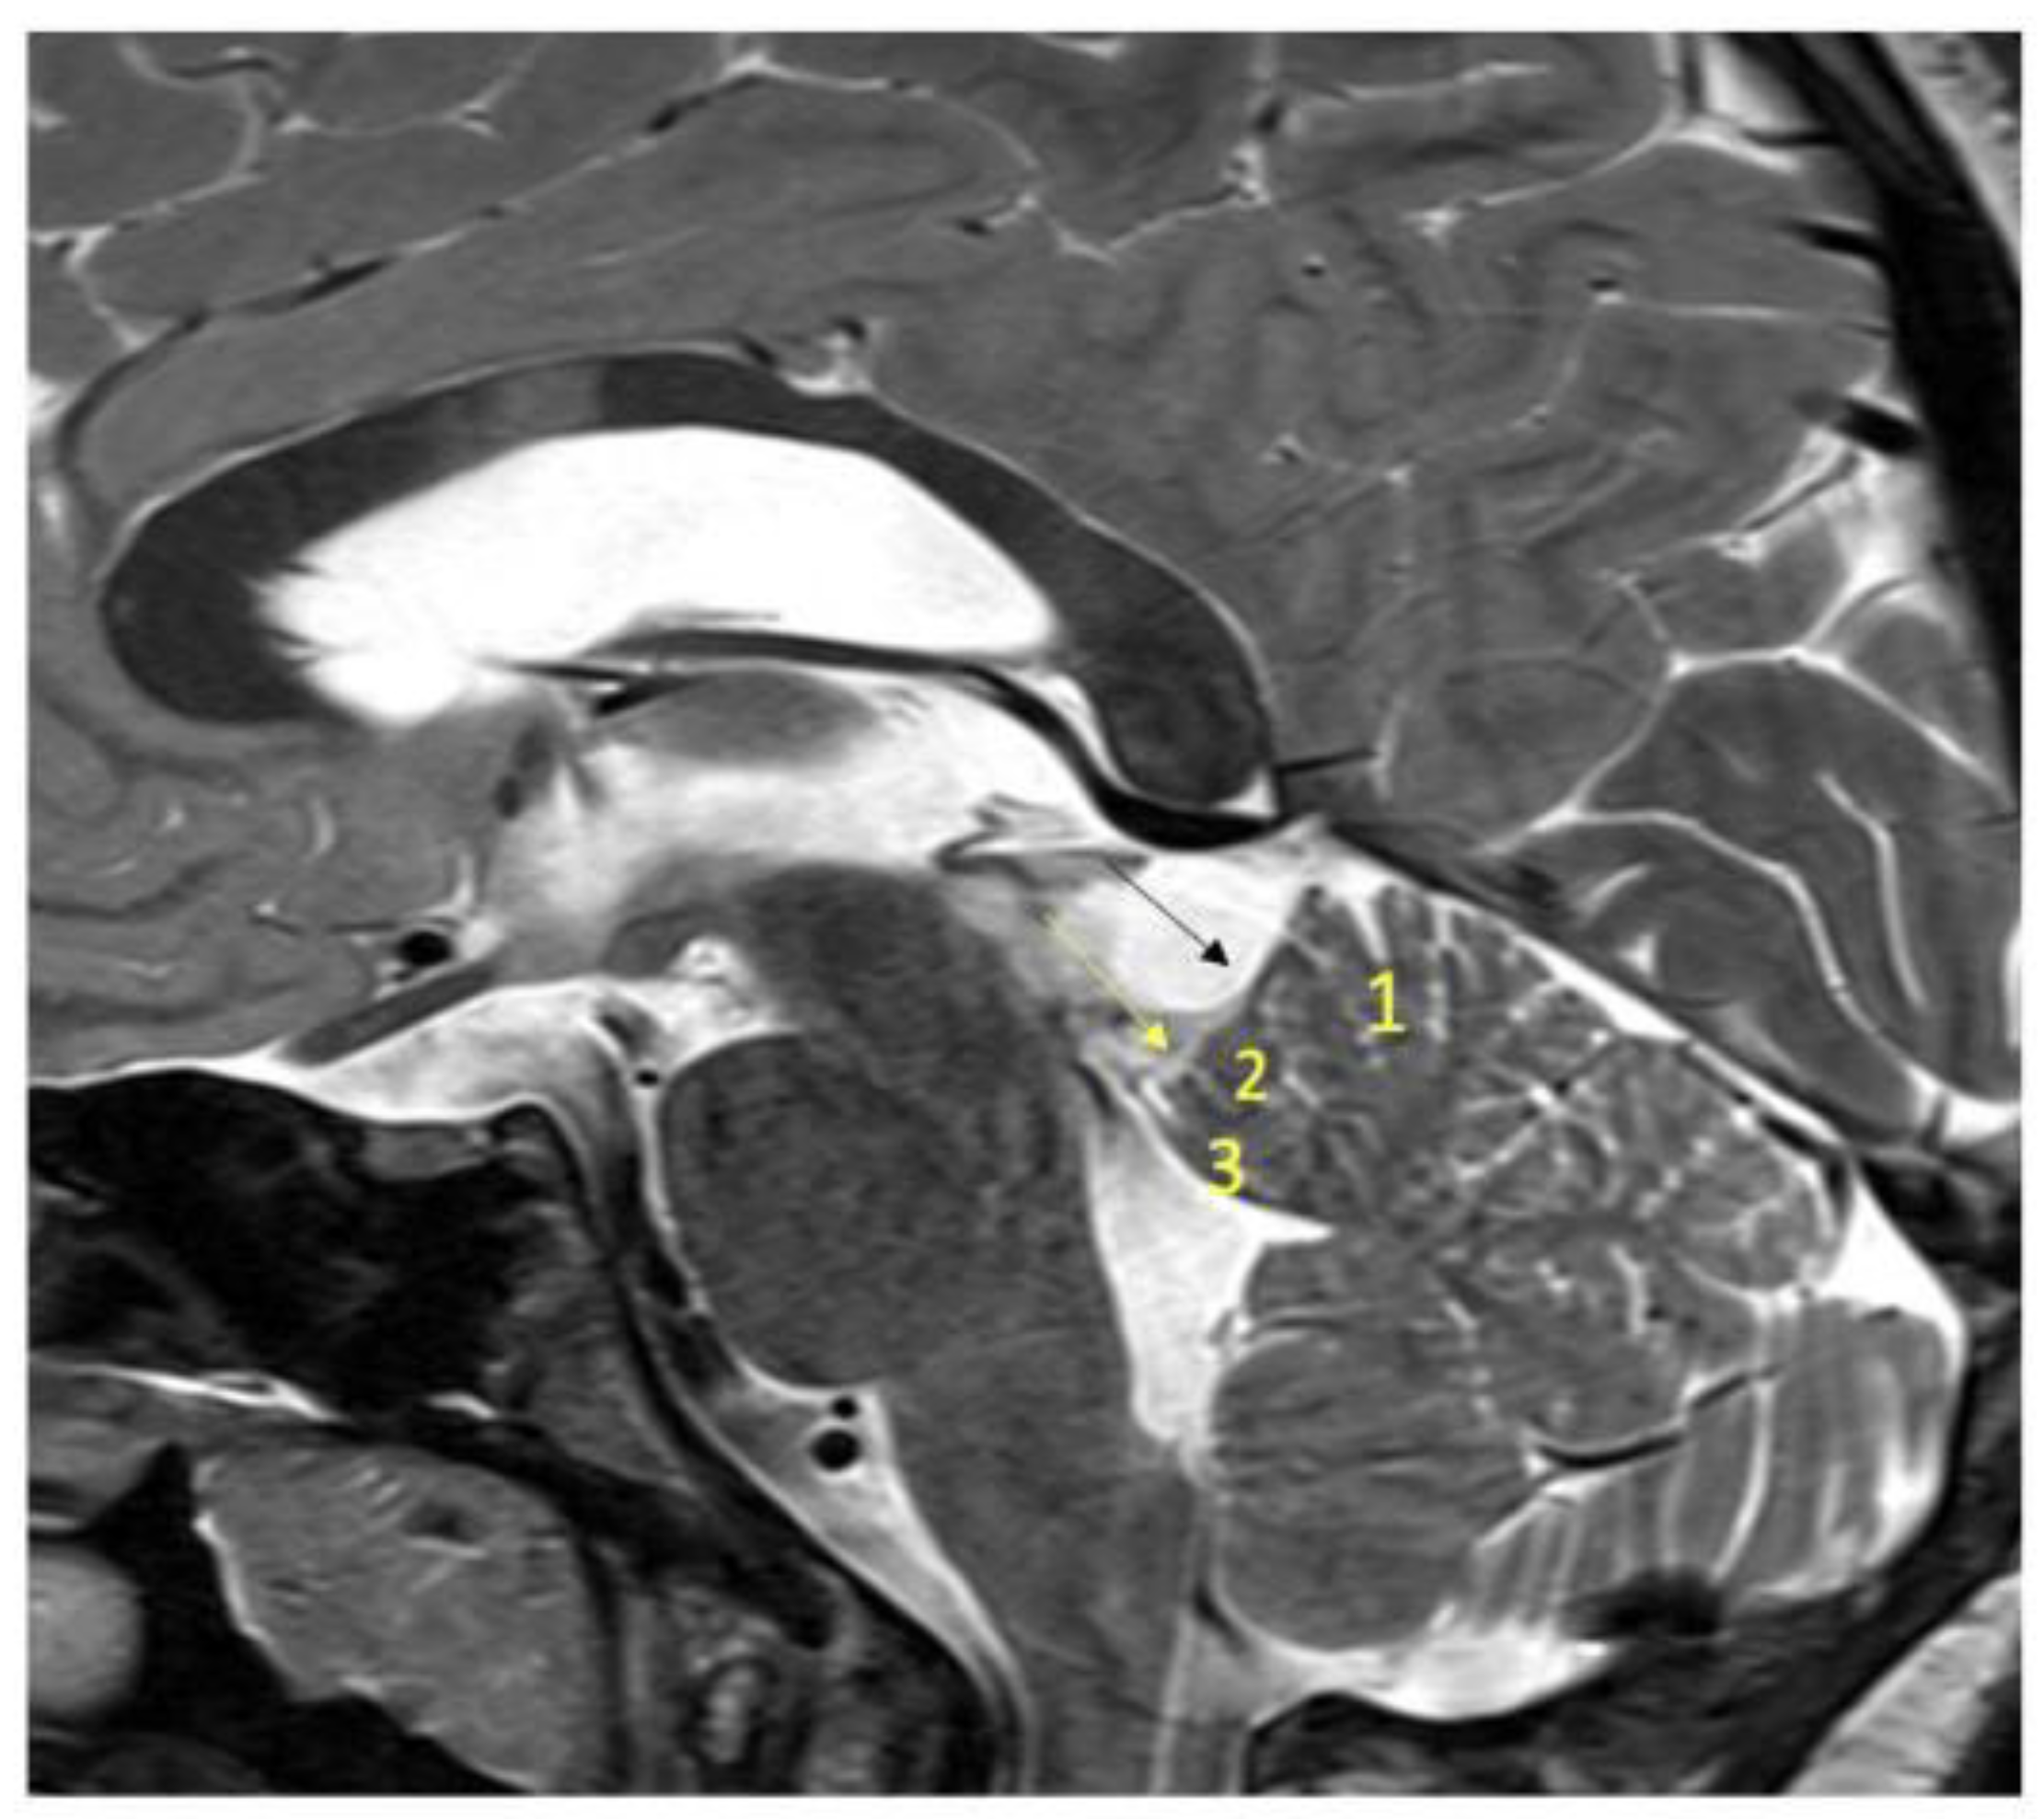

3. Operative Technique